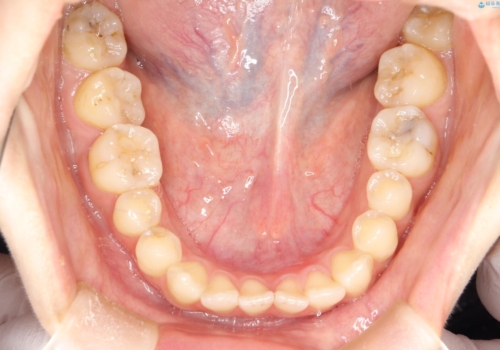

- 治療計画